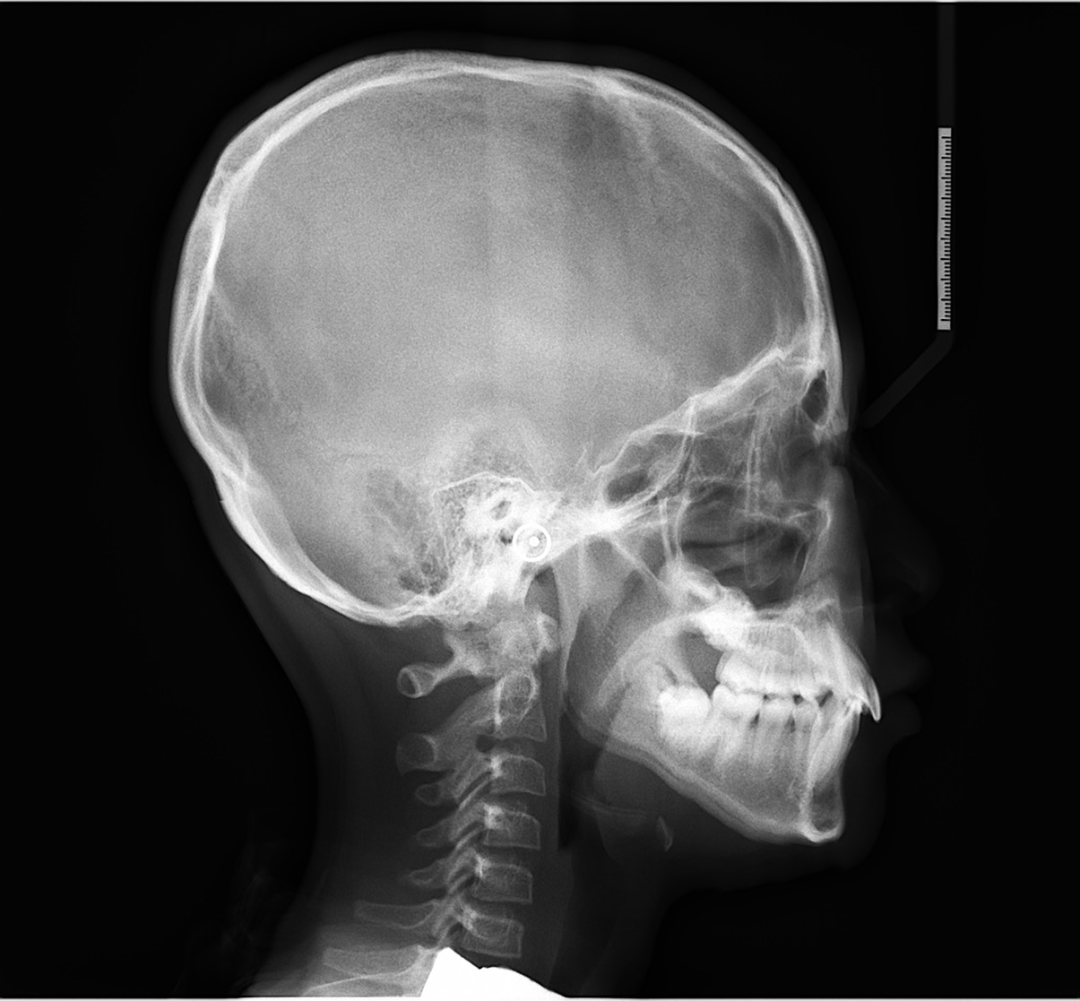

如果孩子闭锁性深覆合的问题,尤其是上前牙覆盖下前牙,甚至内扣盖住下前牙,如果孩子是高角或者是高角偏均角的话,这个就容易出现未来下颌骨发育的受限。

但如果发现是典型的低角,那么孩子颏部形态长得会比较好,只是因为下前牙唇倾会导致下巴被迫后退,当早期矫正改善下前牙位置后,孩子的下巴自然而然就会出来了。

其实这也是错颌畸形先天基因的表达和后天相关影响,这两个因素作斗争时谁会更强的结果吧。因此出现闭锁性深覆合,在5岁左右或者替牙期换完上下门牙时进行矫正,可以引导牙齿和颌骨的正常生长,还有机会改变骨骼生长型。在生长发育过程中,由于遗传因素、环境因素、口呼吸习惯等导致颌骨发育异常,会出现上颌前凸、下颌后缩、腭盖高拱、腺样体面容等问题。

这些异常不仅影响美观,还会影响口腔的咬合功能,在替牙期换完上下门牙时,也就是8-9岁左右进行矫正,有机会利用儿童骨骼生长潜力,调整颌骨位置关系,促进颌面部正常发育,还能锻炼孩子正确的唇舌肌习惯。